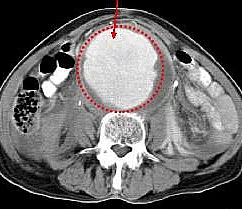

대동맥류의 진단

대동맥류는 초음파, CT, 혈관조영술로 진단할 수 있습니다.